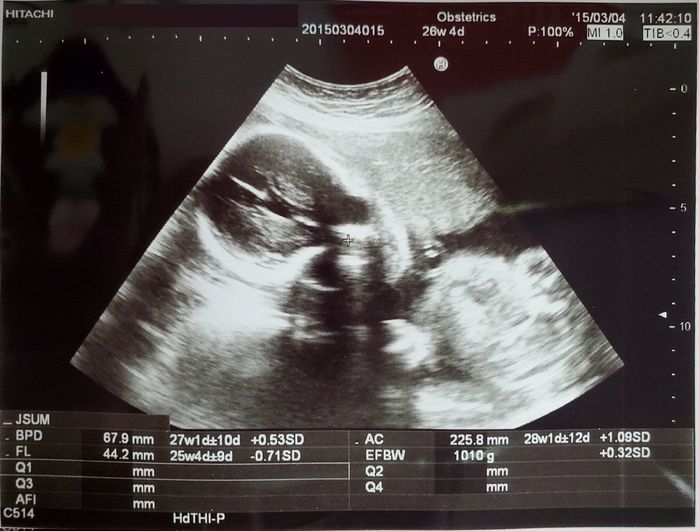

妊娠26週目のエコー写真 - 推定体重が1000gを超えました

EFBW(胎児推定体重)がついに1000gを超えました。胎動も感じ方が強くなり、赤ちゃんが元気だと思うと嬉しかったです。エコーでは相変わらずこちらを向いていて、手をふっているようにも見えますし、笑っているようにも見えます。このころからおなかが張る事が増え、なかなか眠れなくなりました。